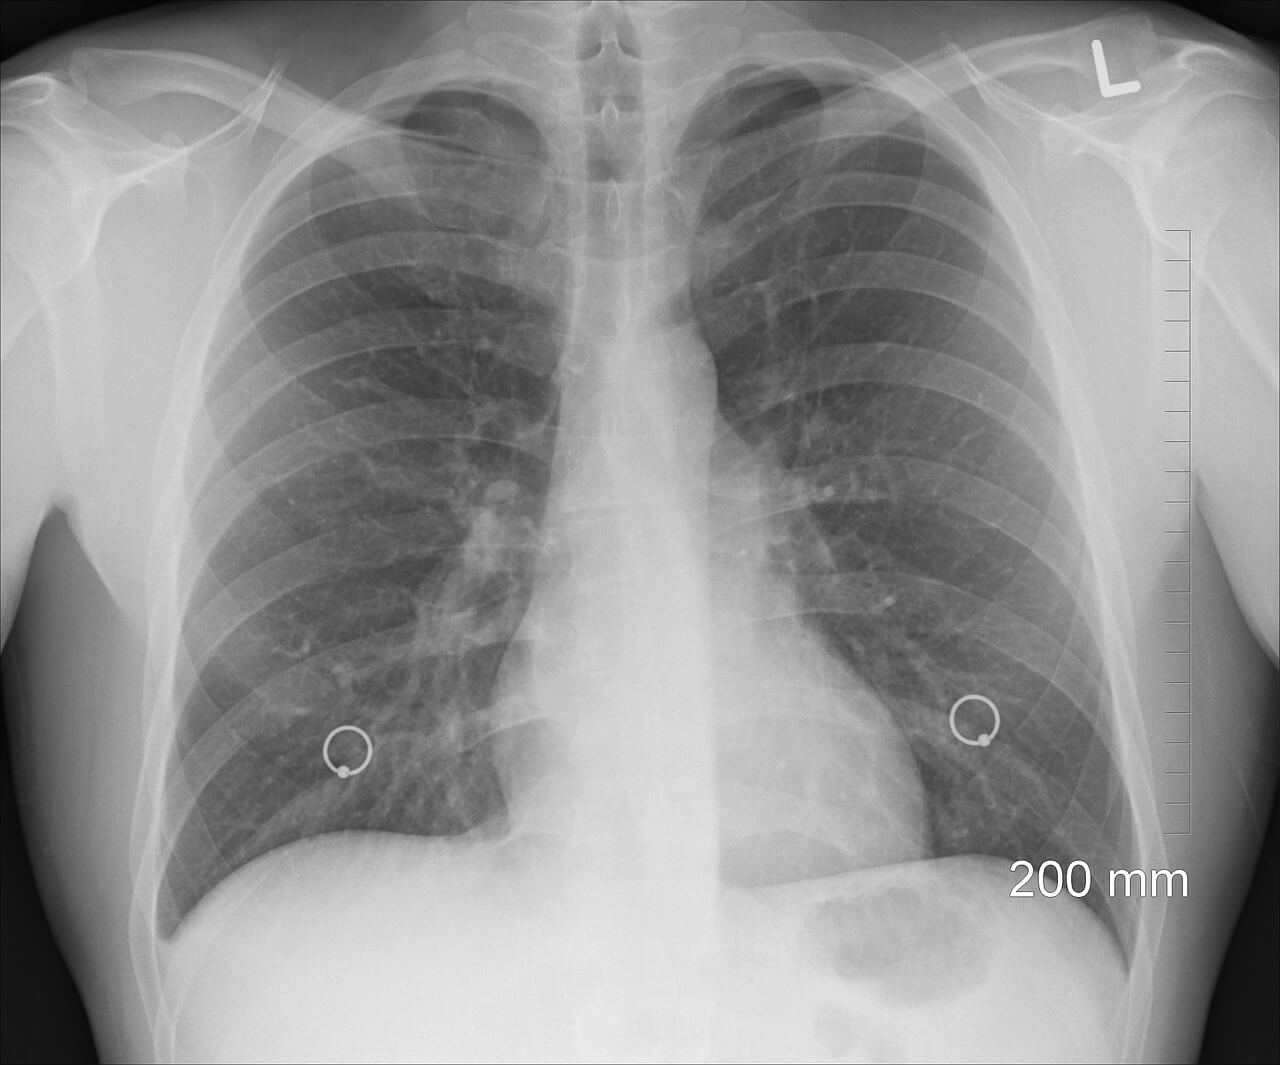

3-2. 흉부 X선

일반 건강검진에 포함되지만, 초기 폐암은 발견률이 낮기 때문에 CT와 병행해야 합니다.